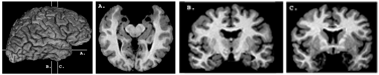

MRI scans of brain

Left: MRI scans of the brain of patient S.M., showing the amygdala lesions. The section numbers (A,B,C) correspond to the planes indicated on the whole brain image shown in the upper left. The lesion can be appreciated in section C. by comparison to the intact orange amygdala on the left, and can also be seen as two symmetrical "holes" in section A.